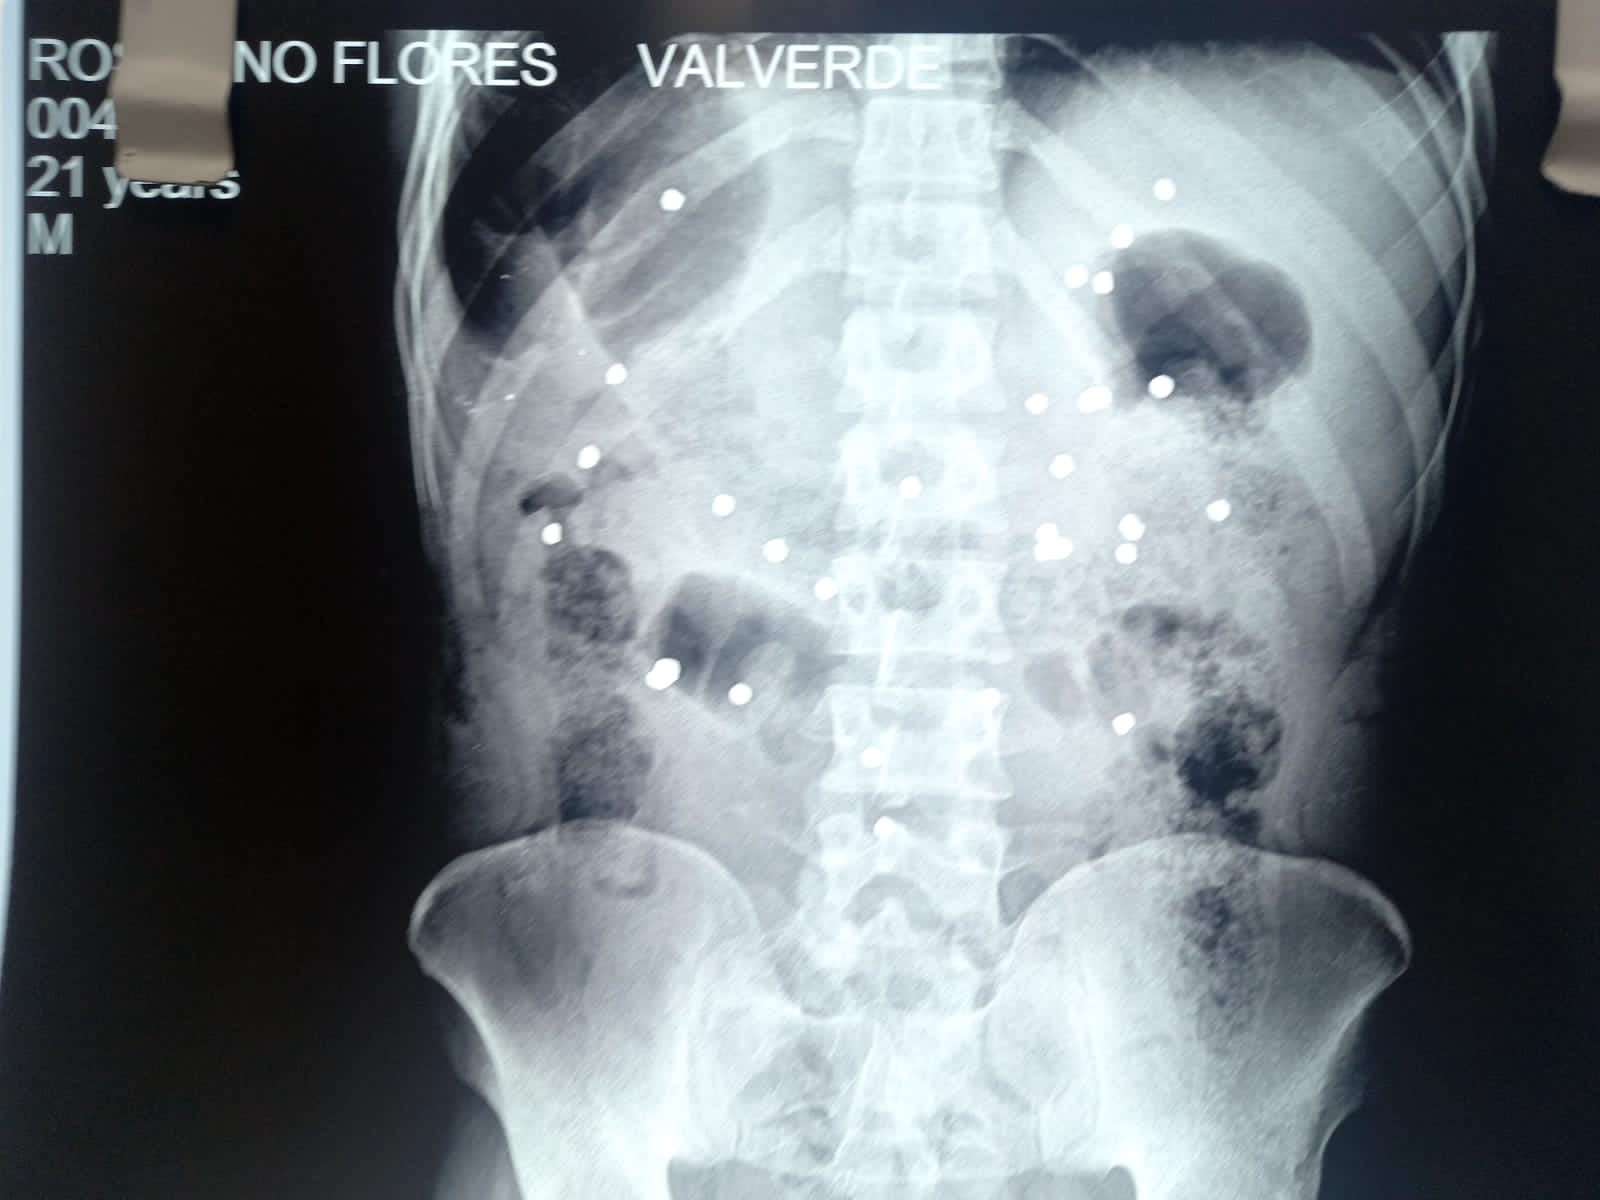

Radiografía que muestra perdigones en el cuerpo de Rosalino Florez.